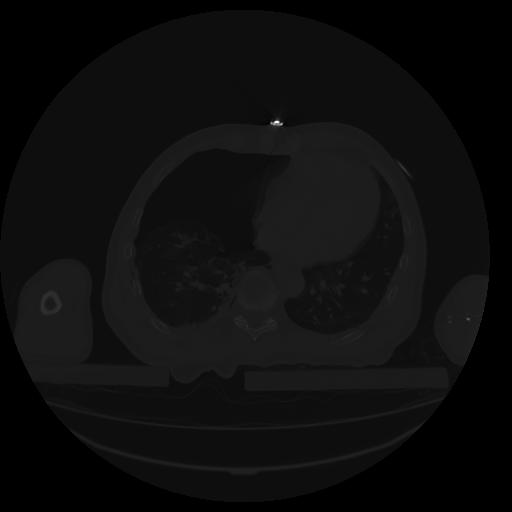

27 CUERPO,CE,Axial,3.0,CUERPO,,